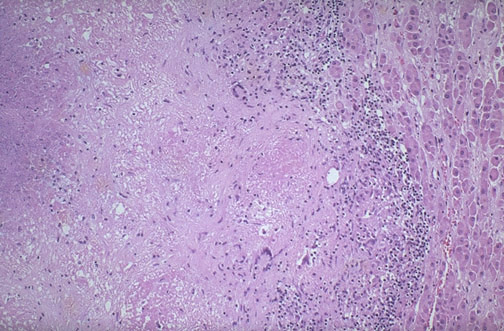

| Years ago, and still today in places with a high incidence of active tuberculosis with dissemination from the lungs, the most common cause for Addison disease is granulomatous inflammation and adrenal cortical destruction. Infections such as histoplasmosis can produce similar findings. Note the caseous necrosis, the Langhans giant cells, and the residual cortex seen here. |